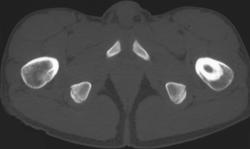

Necrotizing Fasciitis